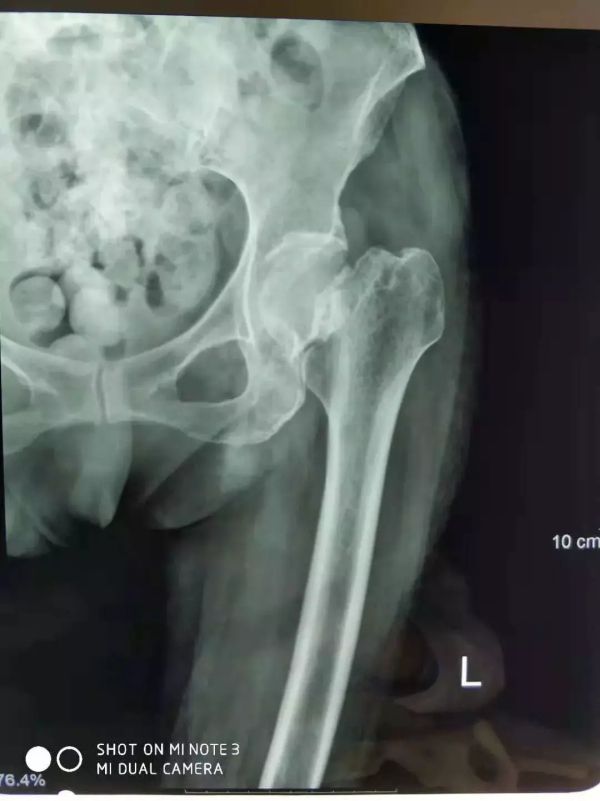

醫(yī)院片子

患者臥床兩個(gè)月后骨折移位更大了